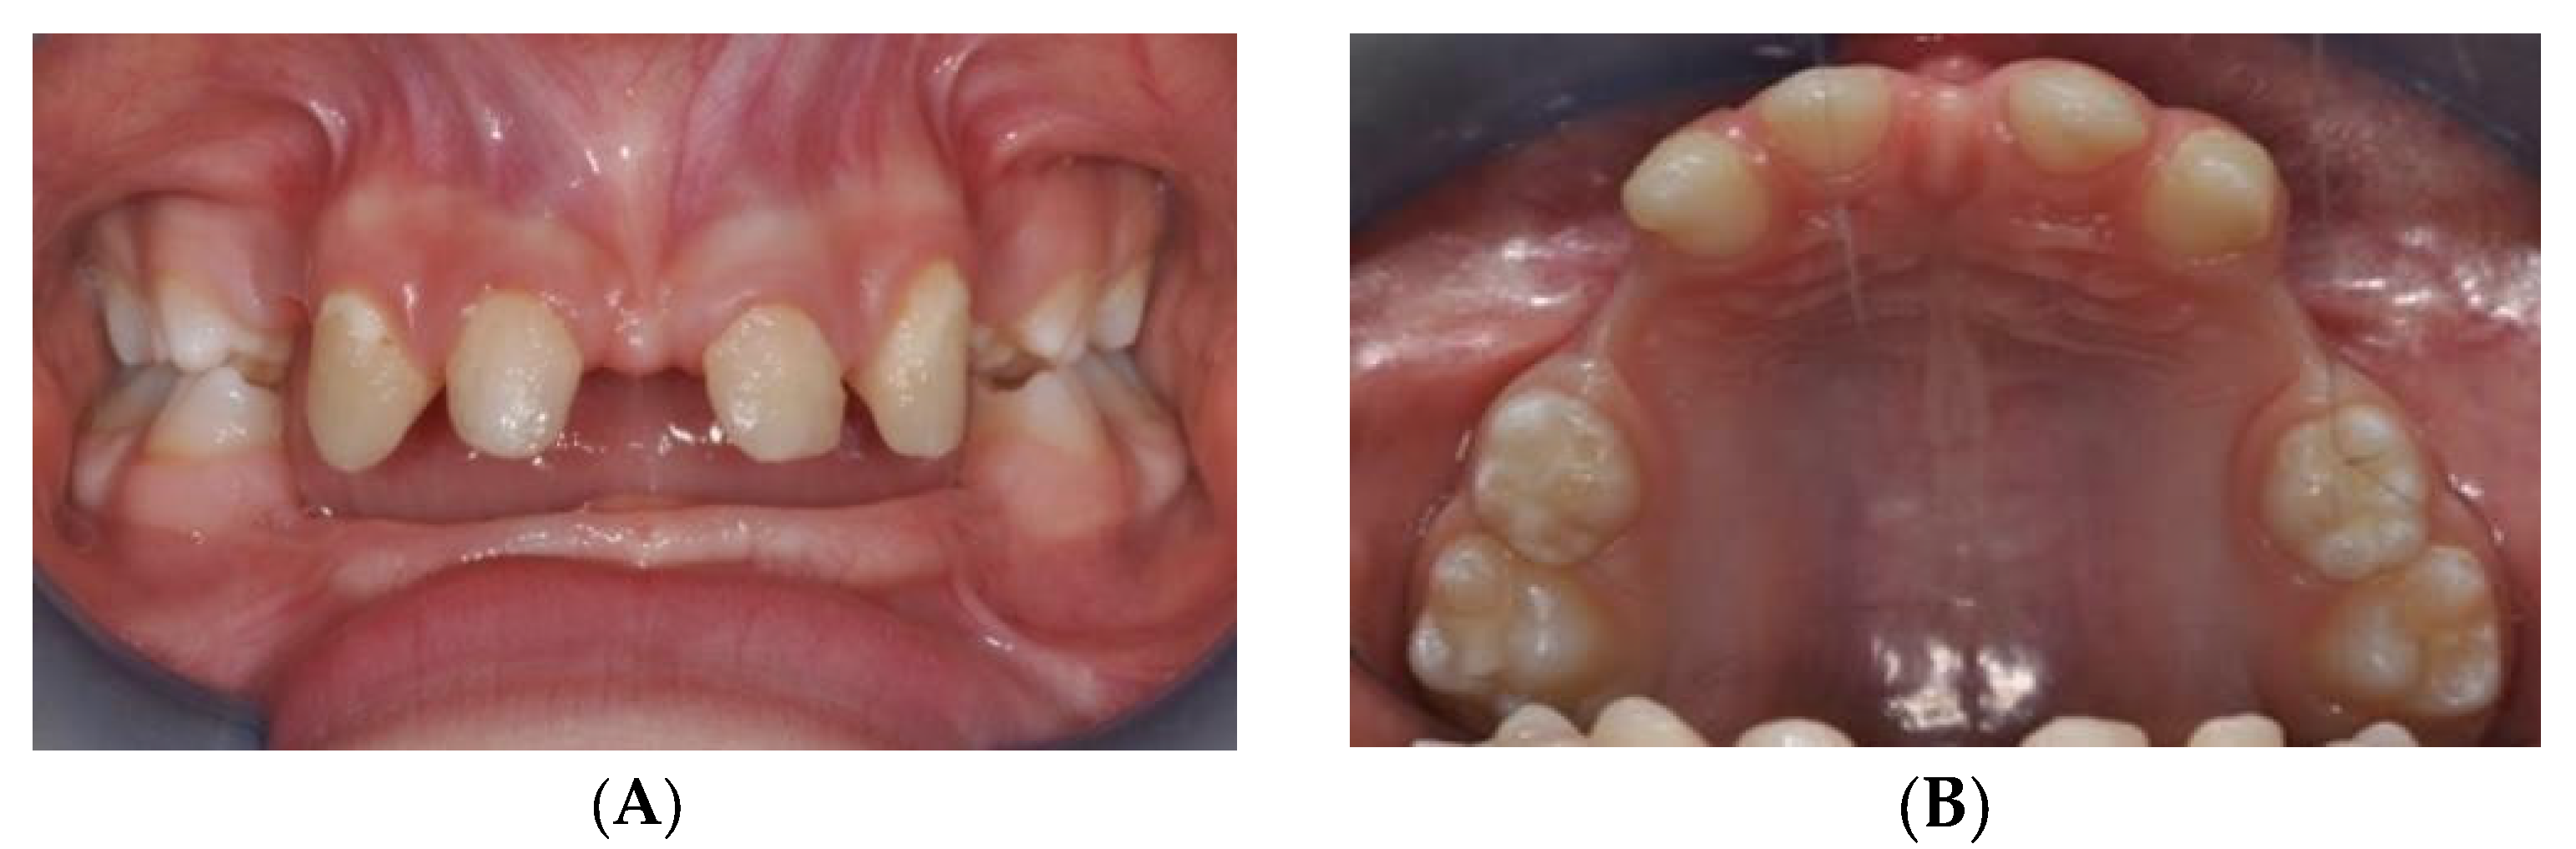

2.1. MSE Treatment in Patient with Ectodermal Dysplasia

2.2. MSE Treatment in Patients with Osteogenesis Imperfecta and Dentinogenesis Imperfecta